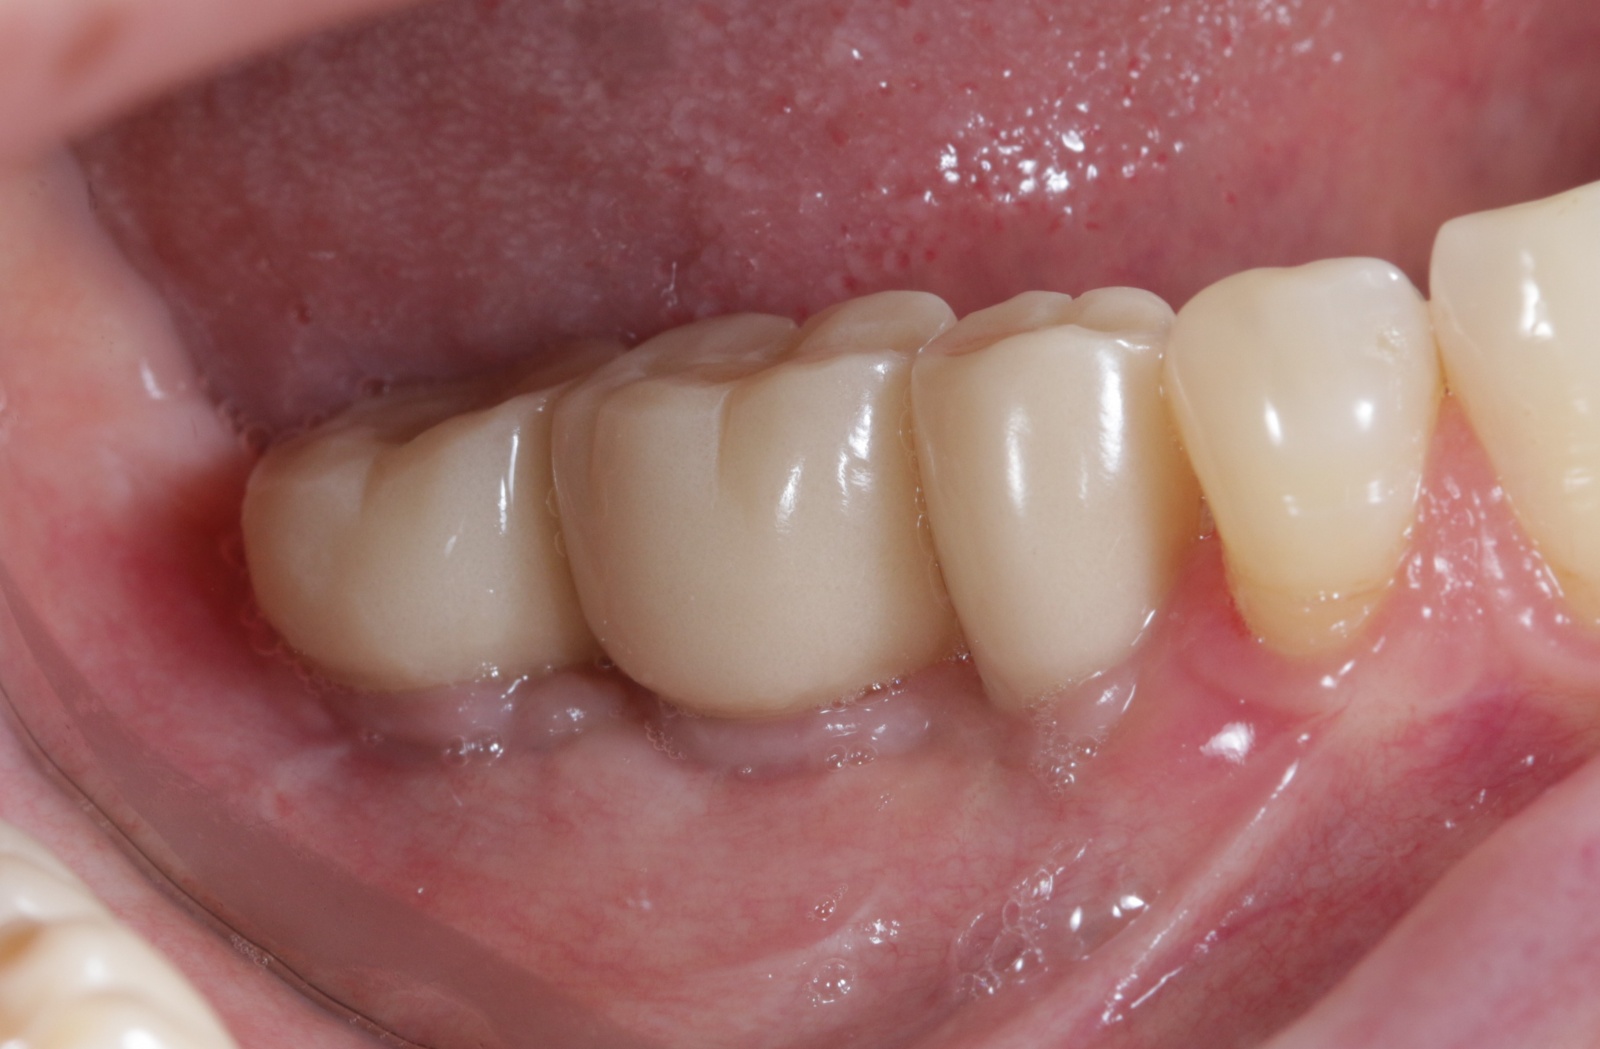

С точки зрения обывателя всё в порядке, а по факту косяк, который сложно будет исправить.

Вот фрагмент компьютерной томографии.

Имплантат стоит под серьёзным наклоном. Его ось не соответствует осям «родных» зубов. Нагрузка по принципу рычага распределяется неправильно, да и коронка имеет неправильную анатомическую форму — с нависающими краями, под которые забивается пища и зубной налет.

Развивается воспаление и, как следствие, убыль костной ткани и десны вокруг имплантата. Мало кто из вас хотел бы заплатить деньги за работу, которая в итоге пойдет по бороде. Даже индивидуальные абатменты тут не помогут.